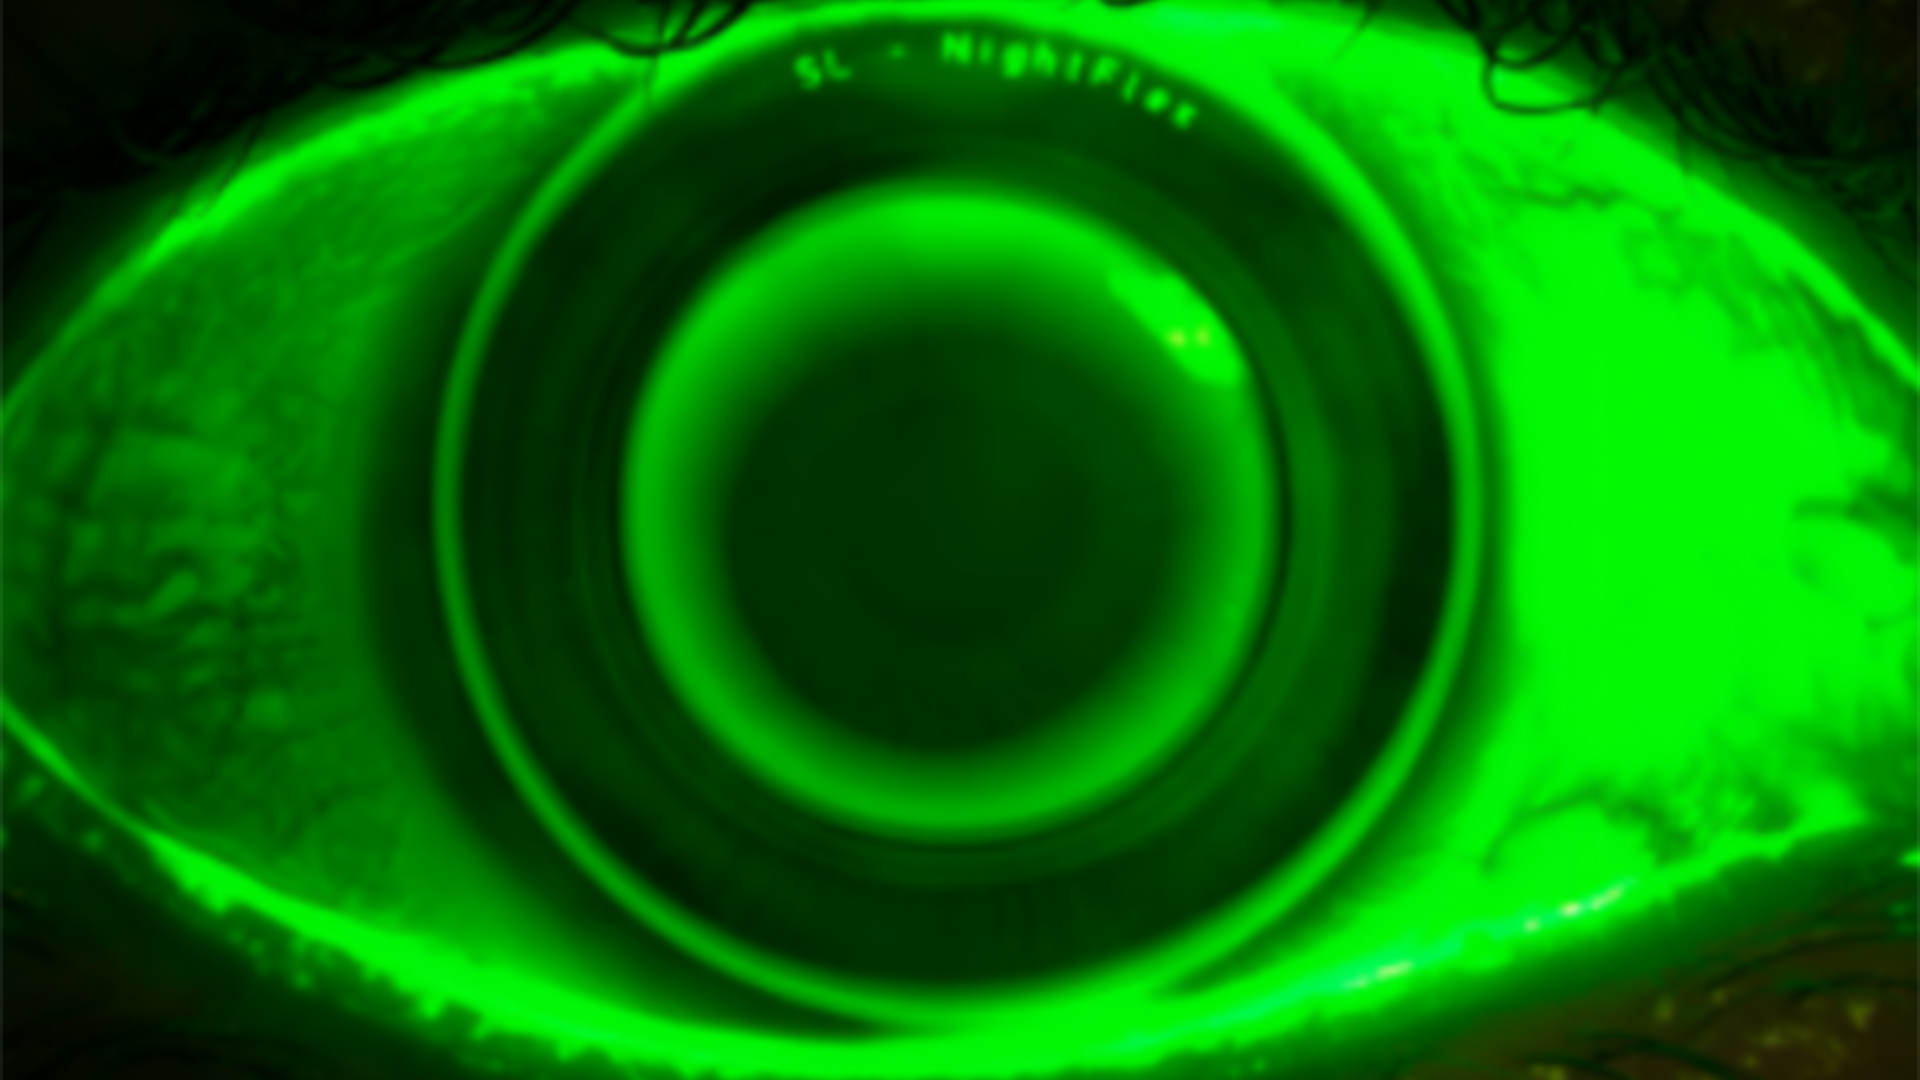

Ortho-K: Troubleshooting und Anpassfälle aus dem Alltag

Stoßen Sie manchmal an die Grenzen von Orthokeratologie Systemen? Ist es für Sie wichtig auch Kinder optimal und im Rahmen eines Myopiemanagements zu versorgen? Dann sind Sie hier genau richtig! Wir verschieben Ihre Grenzen und üben gemeinsam auch die Kleinsten sicher und zum Vorteil der Augengesundheit zu versorgen.

• Umgang mit der Spaltlampe

• Versorgungskenntnisse mit Ortho-K

• Topographie